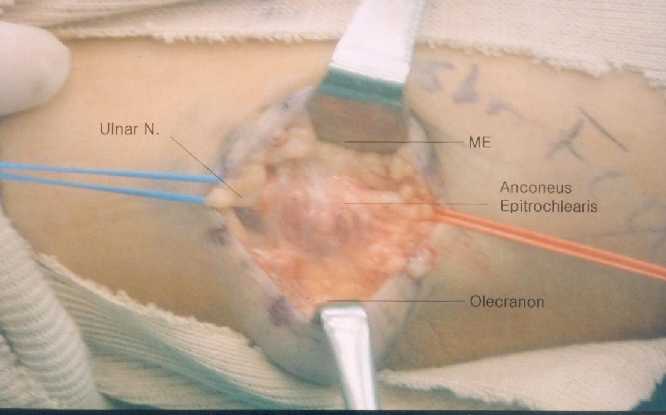

At exploration of the left cubital tunnel, a group of muscle fibers approximately 3-centimeter in width and 3-centimeter in length

(Figure 1)

crossed the ulnar nerve from olecranon to medial epicondyle, which was found to be the anconeus epitrochlearis muscle. The ulnar nerve was compressed by the aberrant muscle and a fusiform thickening and induration of the nerve trunk were observed just proximal to the muscle. The muscle was tight in flexion and significantly compressed the ulnar nerve. The ulnar nerve was strained proximal to the muscle bulk at elbow flexion beyond 90. The aberrant muscle was split longitudinally and flexor retinaculum as well. Splitting of the muscle revealed the aberrant muscle was hypertrophied as thick as 5 millimeter in depth and compressed the nerve during elbow flexion. It disclosed narrowed area of ulnar nerve 10mm under the muscle

Figure 1 .